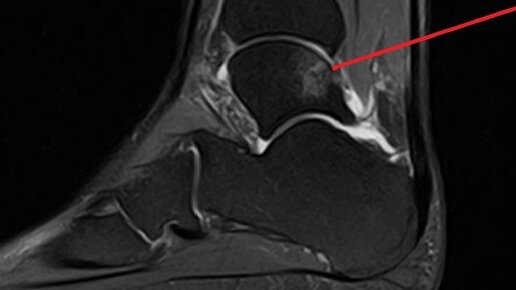

Голеностопный сустав и повреждения костной ткани

Продолжим разбирать голеностопный сустав и прилегающие к нему структуры, а так же разберём повреждения, связанные с контузиями костной ткани и перегрузочными явлениями.  С развитием тренда спортивного образа жизни, становится всё более актуален вопрос болей, связанных с избыточной нагрузкой на нижние конечности. В основном это связано с тем, что самым простым и доступным видом активной деятельности, является бег, причём бег на улице. В условиях города это сопряжено с не самой благоприятной поверхностью...